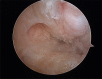

Material and methods: Of the 22 patients who were treated; 18 males and 4 females, and aged from 17-42 years (mean 28 years). All patients presented a history of more than three ankle sprains in the last two years and presented positive anterior drawer and talar tilt test of the ankle in the physical examination. We perform an anterior arthroscopy of the ankle in order to treat asociated disease and then we performed "All inside¨ lateral ligament repair through two portals (anteromedial and anterolateral) using an anchor knotless suture.